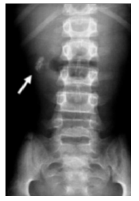

Considere a imagem a seguir:

A radiografia simples de abdome acima evidencia imagens radiopacas no hipocôndrio direito caracterizando: